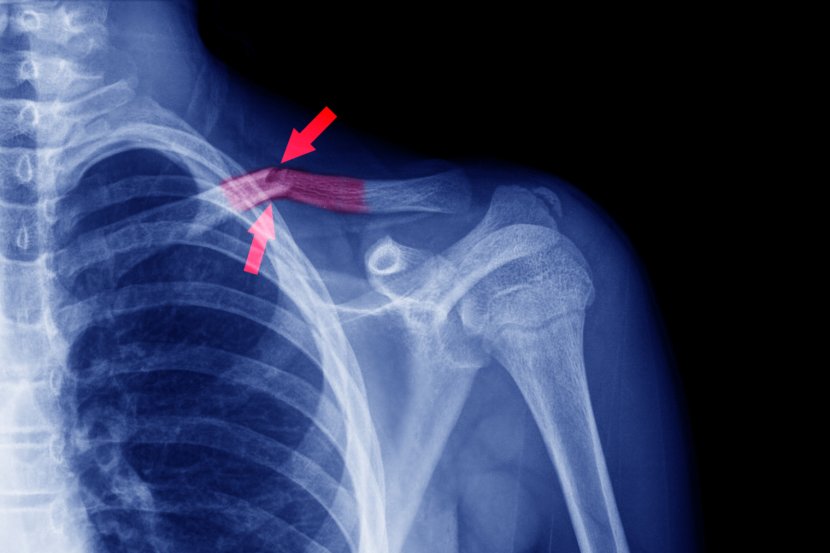

Ključna kost ili klavikula je jedna od kostiju u telu koja se najčešće lomi. Simptomi slomljene ključne kosti su jak bol i otok na mestu preloma, sa vidljivim deformitetom u nekim slučajevima. Prelom ključne kosti dijagnostikuje se fizičkim pregledom i rendgenskim snimkom, a prelomi su klasifikovani u tri tipa, na osnovu lokacije preloma.

Kada se kosti lome, dolazi do otoka zbog krvarenja iz krvnih sudova oko kosti. Javlja se i bol zbog  slomljene kosti zbog oštećenja mikroskopskih nervnih završetaka oko kosti. Ponekad je kost tako slomljena da stvara ugao između slomljenih krajeva, što uzrokuje deformitet duž kosti. Obično su kod slomljene ključne kosti bol i otok jaki i deformitet može da bude vidljiv. Često se javlja bol na mestu preloma sa svakim pokušajem pomeranja ruke. Jedini način da se ustanovi da li je kost polomljena je rendgenski snimak tog područja.

Prva stvar koju će lekar uraditi je rendgenski snimak kako bi utvrdio da li je ključna kost slomljena, gde se prelom nalazi i na koliko delova je kost polomljena. Prelomi ključne kosti se u osnovi dele na tri tipa, i to na osnovu lokacije:

• prelomi u blizini grudne kosti su najmanje česti (manje od 5 procenata svih preloma ključne kosti)

• prelomi blizu AC zgloba su drugi najčešći i mogu se pojaviti u mnogo različitih obrazaca

• najčešći prelomi klavikule su u sredini osovine kosti, otprilike na pola puta između grudne kosti i AC zgloba.